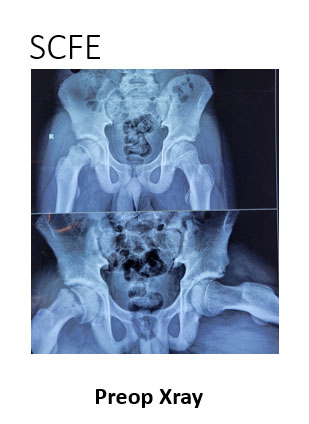

SCFE